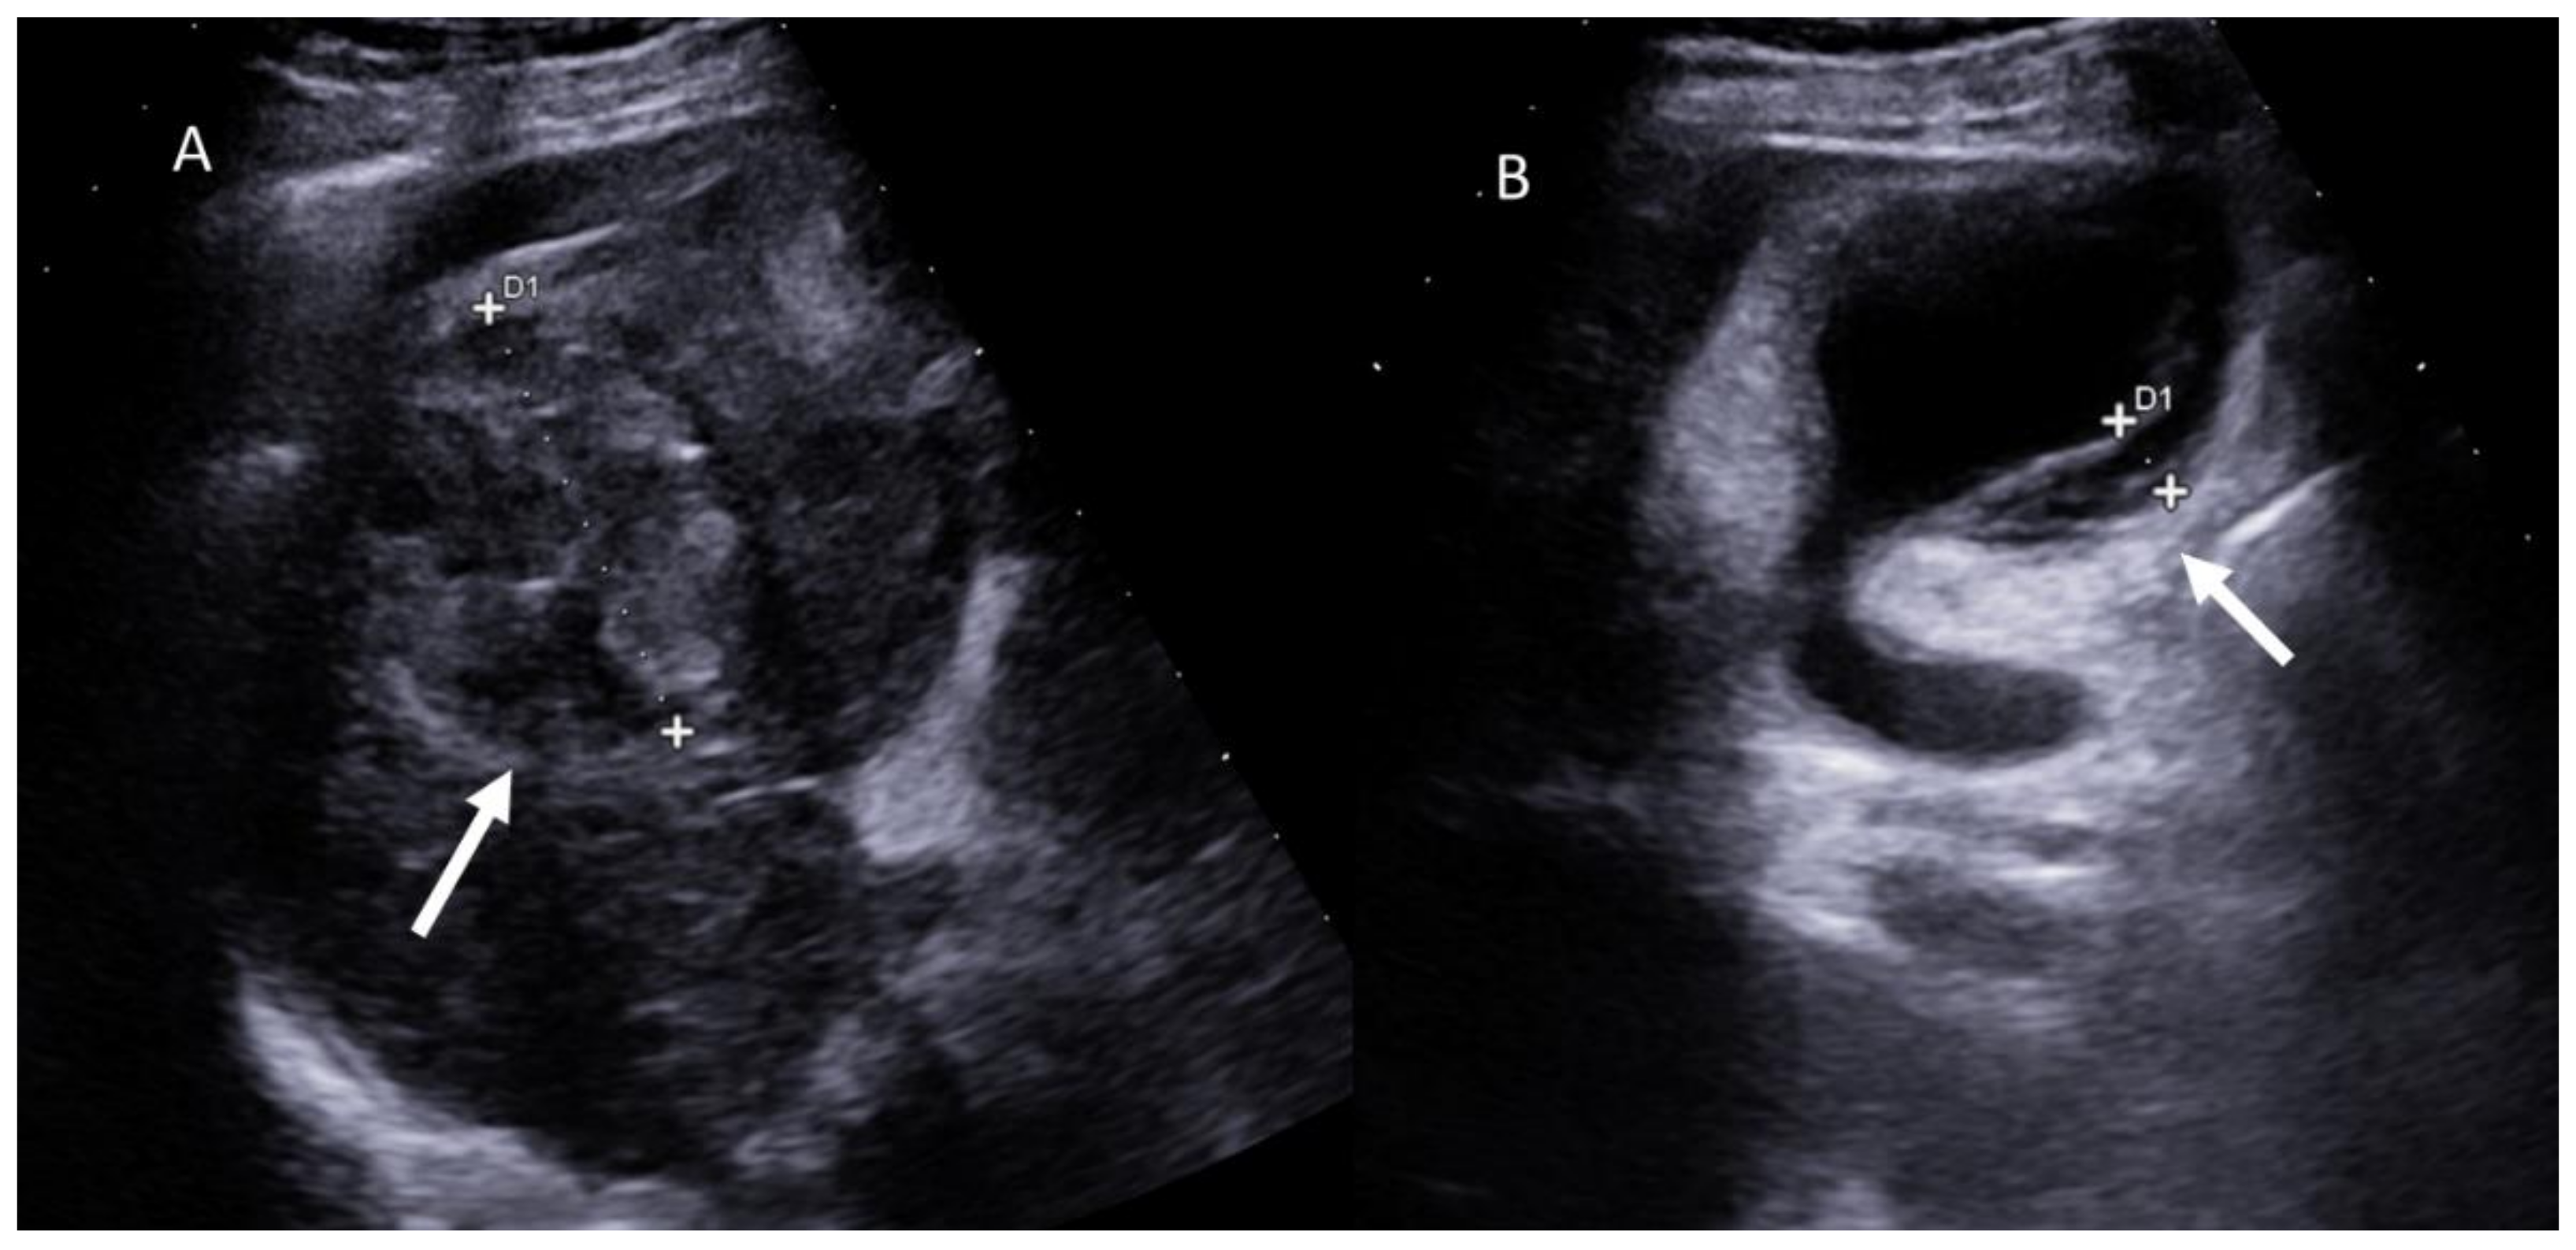

- Minami, Y.; Minami, T.; Hagiwara, S.; Ida, H.; Ueshima, K.; Nishida, N.; Murakami, T.; Kudo, M. Ultrasound-ultrasound image overlay fusion improves real-time control of radiofrequency ablation margin in the treatment of hepatocellular carcinoma. Eur. Radiol. 2018, 28, 1986–1993. [Google Scholar] [CrossRef]